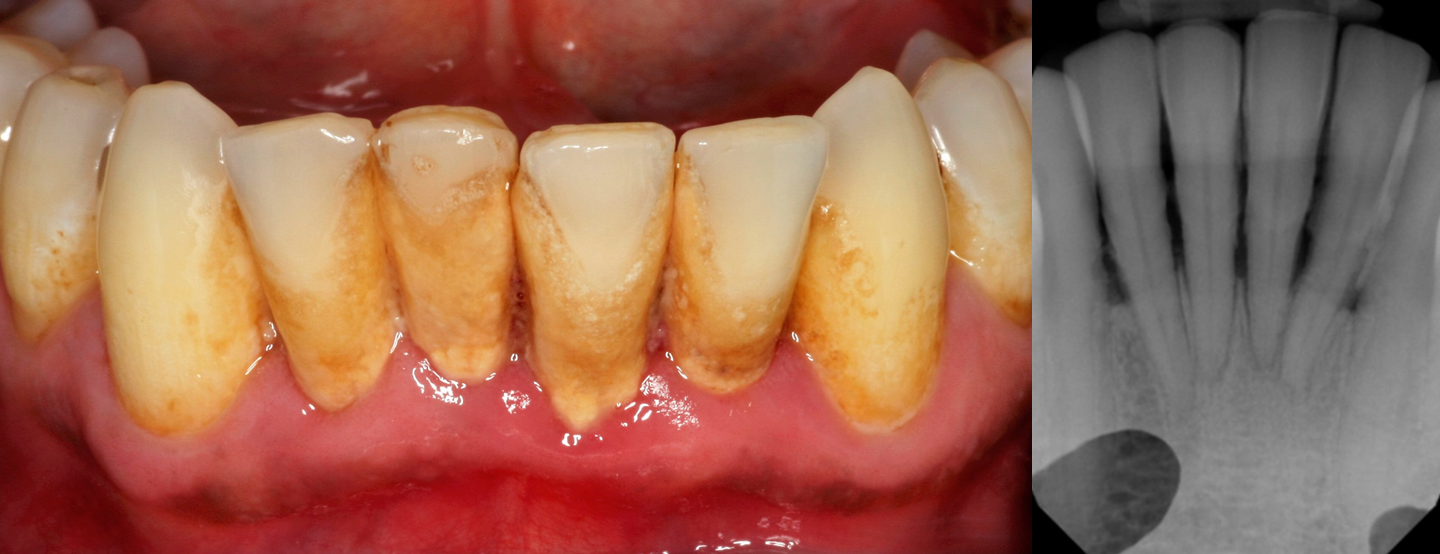

Rampant Dental Caries

Rampant tooth decay is a condition in which multiple teeth have generalized and rapidly growing cavities (see Figure 14). It also can be referred to as severe tooth decay.6,7

![]() |

Class 5 cavities on the upper teeth |

The main cause is not brushing or flossing on a routine basis. High sugar consumption, including sodas, sports drinks, and candy, contribute significantly to severe tooth decay. Some medications can cause dry mouth (xerostomia), that can lead to tooth decay. Radiation therapy to the head and neck also can cause tooth decay.6,7,9

Severe tooth decay can produce discomfort, sensitivity, and pain. If teeth are not treated with endodontics, the pulp chamber becomes infected and an abscess forms. This contributes to tooth loss and decreased function. This can be treated by referring the patient to a dentist or endodontist who will remove the diseased portion of the tooth pulp, placing a material in the pulp chamber and thus save the tooth for further treatment.6,7

When the patient presents with rampant caries, they should be counseled to practice good oral hygiene, including brushing and flossing. Brushing should be in a circular motion with the brush pointed at a 45-degree angle toward the gums for a minimum of three minutes (Bass technique), at least twice per day. The patient also should use their toothbrush to massage their gums. The palate and tongue also should be cleansed. The patient’s toothbrush should be thoroughly rinsed and placed in an upright position.6,7